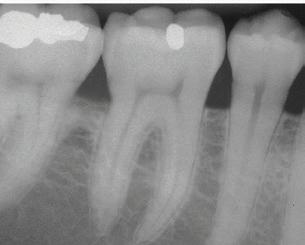

THE AMERICAN ACADEMY OF PERIODONTOLOGY UPDATES DISEASE CLASSIFICATIONS

Recognizing and treating periodontal disease in its earliest stages results in better patient outcomes and has been shown to positively affect the long term whole-body health of patients. Early disease recognition and management can only be accomplished by performing a thorough comprehensive exam which includes, but is not limited to, an oral cancer exam, full mouth pocket charting, and radiographs with a clear view of the interdental crestal bone. As clinicians, we know radiographic bone loss, no matter how minor, is a result of a long-standing infection in periodontal tissue.

The culture of the hygiene program at Falcon Park Dental Group is proactive. We will quit watching and start treating. Our providers will link periodontal conditions to medical conditions and will refer to primary care physicians for unresolved inflammation. We will help our patients understand that bone loss is not a symptom; it is a RESULT. When we see bone loss on an x-ray, it is more destructive than it appears. We will also commit to using salivary diagnostics when indicated. We have committed ourselves to helping our patients understand that we must treat periodontal inflammation before it is too late.

Visually show bone loss through the patient’s own X-rays and/or the educational poster